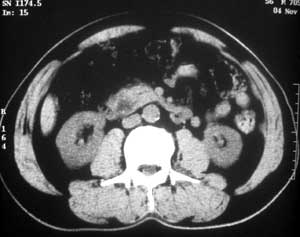

患者,男,57岁,梗阻性黄疸10余天。

这个病例胰头无明显增大,胆总管扩张明显而肝内胆管扩张更不明显,病程较短,

注意到十二指肠乳头明显突出,但尚光滑。分析以下可能性:

1、十二指肠乳头本身的病变,如乳头炎症;

2、急性乳头水肿,胆总管下端结石排石后乳头水肿;

3、壶腹部胆总管下端肿瘤累及十二指肠乳头。

十二指肠乳头粘膜慢性非特异性炎症